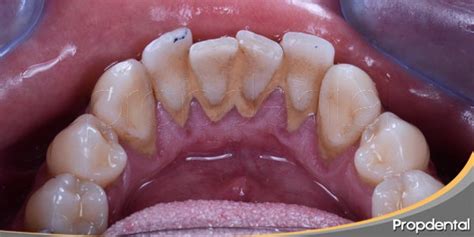

Acumulación de sarro en los dientes.

Además, el área detrás de los dientes inferiores, en particular, es propensa a la formación de sarro debido a la proximidad con las glándulas salivales.

- Anatomía oral: La superficie lingual de los dientes inferiores representa una de las zonas más desafiantes para mantener una higiene bucal adecuada.